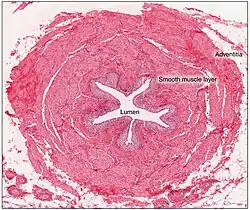

As artérias que irrigam os ureteres terminam em uma rede de vasos dentro da adventícia dos ureteres.[1] Existem muitas conexões (anastomoses) entre as artérias do ureter,[2] principalmente na adventícia,[5] o que significa que o dano a um único vaso não compromete o suprimento sanguíneo do ureter.[2][5] A drenagem venosa em geral é paralela à do suprimento arterial;[5][2] ou seja, começa como uma rede de veias menores na adventícia; com as veias renais drenando os ureteres superiores e as veias vesiculares e gonadais drenando os ureteres inferiores.[1]

Microanatomia

O ureter é revestido por urotélio, um tipo de epitélio transicional que é capaz de responder a alongamentos nos ureteres. O epitélio transicional pode aparecer como uma camada de células em forma de coluna, quando relaxada, e de células mais achatadas, quando distendida. Abaixo do epitélio fica a lâmina própria. A lâmina própria é composta de tecido conjuntivo frouxo com muitas fibras elásticas intercaladas com vasos sanguíneos, veias e vasos linfáticos. O ureter é circundado por duas camadas musculares, uma camada longitudinal interna de músculo e uma camada externa circular ou espiral de músculo.[6][7] O terço inferior do ureter possui uma terceira camada muscular.[7] Além dessas camadas, fica uma adventícia contendo vasos sanguíneos, vasos linfáticos e veias.[7]